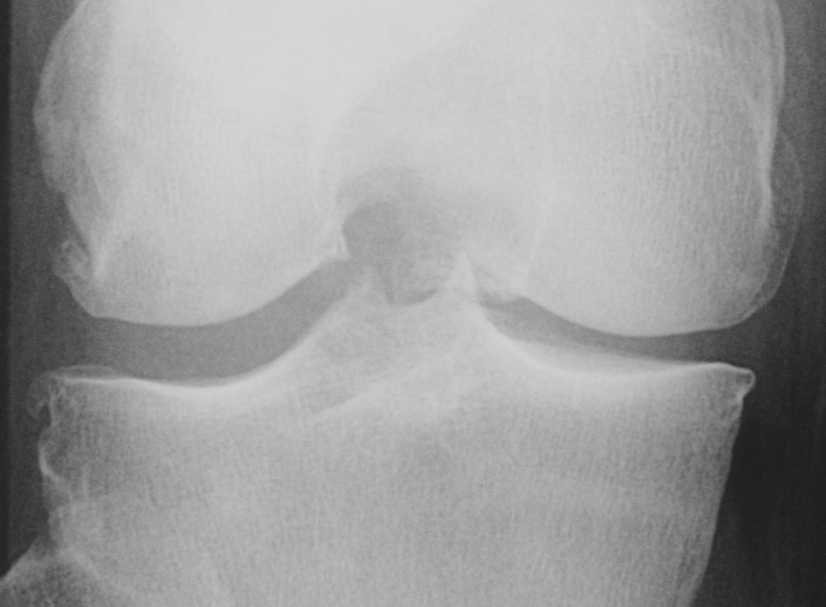

Knee OA develops gradually over years and progresses in stages. In general, the severity of knee OA is divided into five stages. The first stage (stage 0) corresponds to normal healthy knee and the final stage (stage 4) corresponds to the most severe condition (see Figure 2). The most commonly used systems for grading knee OA are the International Knee Documentation Committee (IKDC) system, the Ahlback system, and the Kellgren & Lawrence (KL) grading system. The other widely used non-radiographic knee OA assessment system is WOMAC666Western Ontario and McMaster Universities Osteoarthritis Index, which measures pain, stiffness, and functional limitation. The public datasets, the OAI and the MOST used in this work, are provided with the KL grades and they are used as the ground truth to classify the knee OA X-ray images.

Refer to caption

Figure 2: The Kellgren and Lawrence grading system to assess the severity of knee OA.

The KL grading scale was approved by the World Health Organisation as the reference standard for cross-sectional and longitudinal epidemiologic studies [7, 22, 24, 25]. The KL grading system is still considered the gold standard for initial assessment of knee osteoarthritis severity in radiographs [1, 5, 6, 7]. Figure 2 shows the KL grading system. The KL grading system categorizes knee OA severity into five grades (grade 0 to 4). The KL grading scheme for quantifying knee OA severity from X-ray images is defined as follows [1, 5]:

• Grade 0 : absence of radiographic features (cartilage loss or osteophytes) of OA.

• Grade 1 : doubtful joint space narrowing (JSN), osteophytes sprouting, bone marrow oedema (BME), and sub-chondral cyst.

• Grade 2 : visible osteophytes formation and reduction in joint space width on the antero-posterior weight-bearing radiograph with BME and sub-chondral cyst.

• Grade 3 : multiple osteophytes, definite JSN, sclerosis, possible bone deformity.

• Grade 4 : large osteophytes, marked JSN, severe sclerosis, and definite bone deformity.